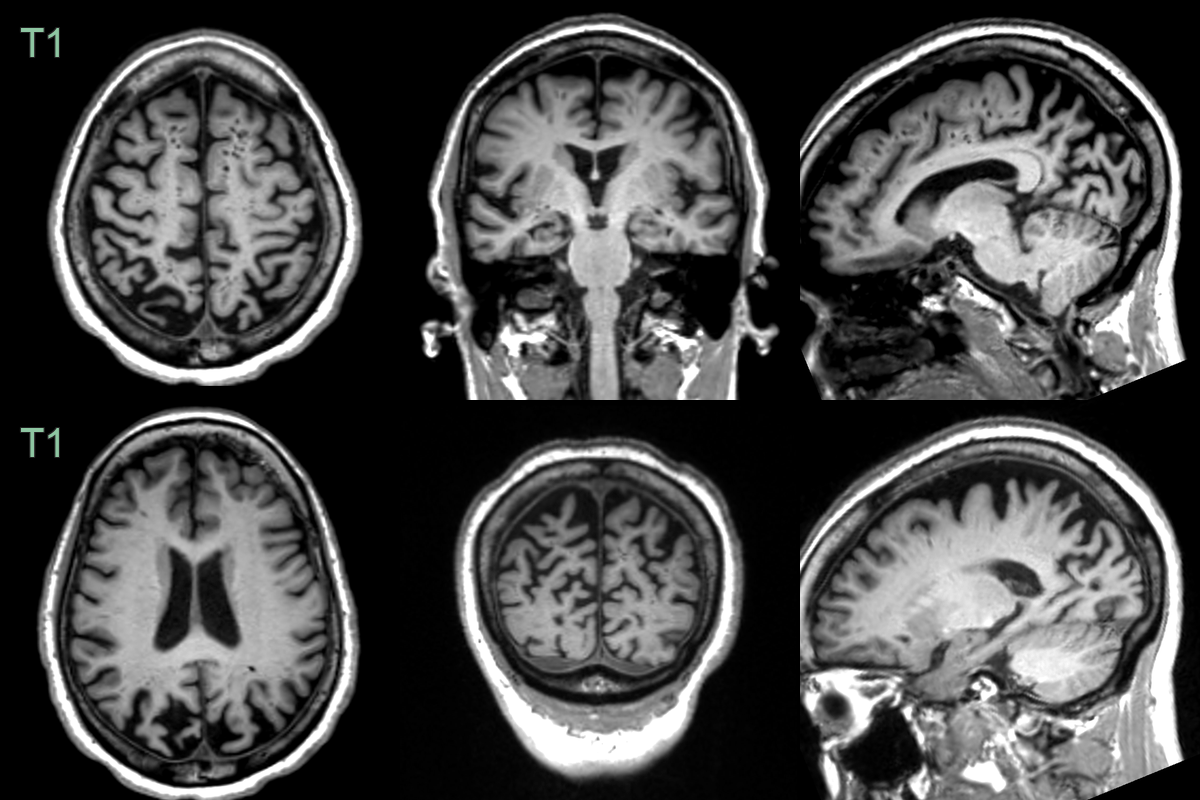

• A 65-year-old patient presented with memory impairment, visual hallucinations and apraxia.

• MRI showed relatively mild hippocampal atrophy on the right but severe symmetrical atrophy of the parietal and occipital lobes.

• CSF biomarkers were compatible with Alzheimer's disease.